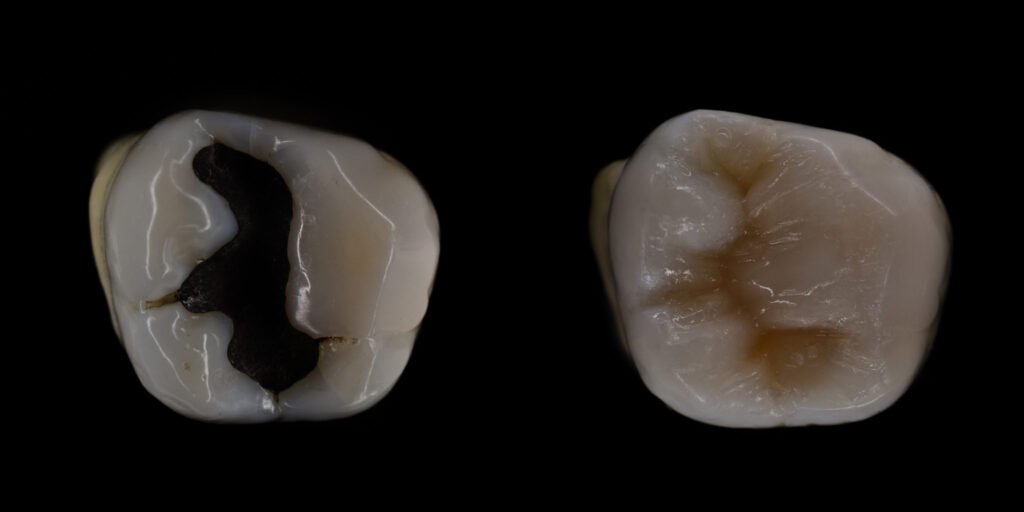

Your journey to a healthier smile begins with a comprehensive consultation at Hardwick Dental Practice. During this visit, our dental professionals will thoroughly examine your teeth and identify any cavities or areas of concern. We will discuss your treatment options and recommend the best type of filling for your specific situation, whether it be composite (tooth-colored), amalgam, gold, or ceramic.

Once the tooth is prepared, we will carefully place the chosen filling material into the cavity. For composite fillings, we use a special light to harden the material, bonding it securely to your tooth. This process restores the tooth’s shape and function while maintaining a natural appearance.